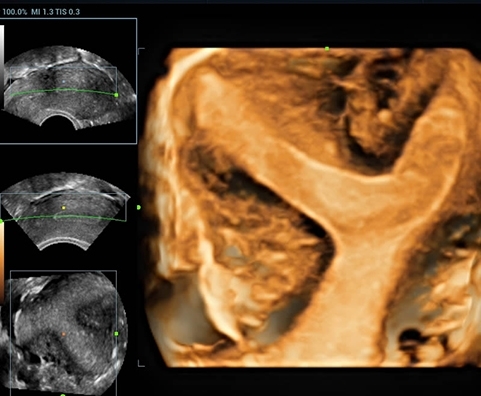

• Echo Basic Package IEC — базовый пакет опций для кардиологии: TDI, Free Xros M, AutoEF, модуль физиологии (включает ЭКГ), DICOM Cardiac SR;

• Echo Advanced Package — расширенный пакет опций для кардиологии: TDI QA, Free Xros CM, Tissue Tracking, Stress Echo (требуется базовый пакет опций для кардиологии);

• 4D Function — модуль объемного сканирования;

• STIC — программное обеспечение для исследования объемного изображения сердца плода с высоким временным и пространственным разрешением;

Изображения